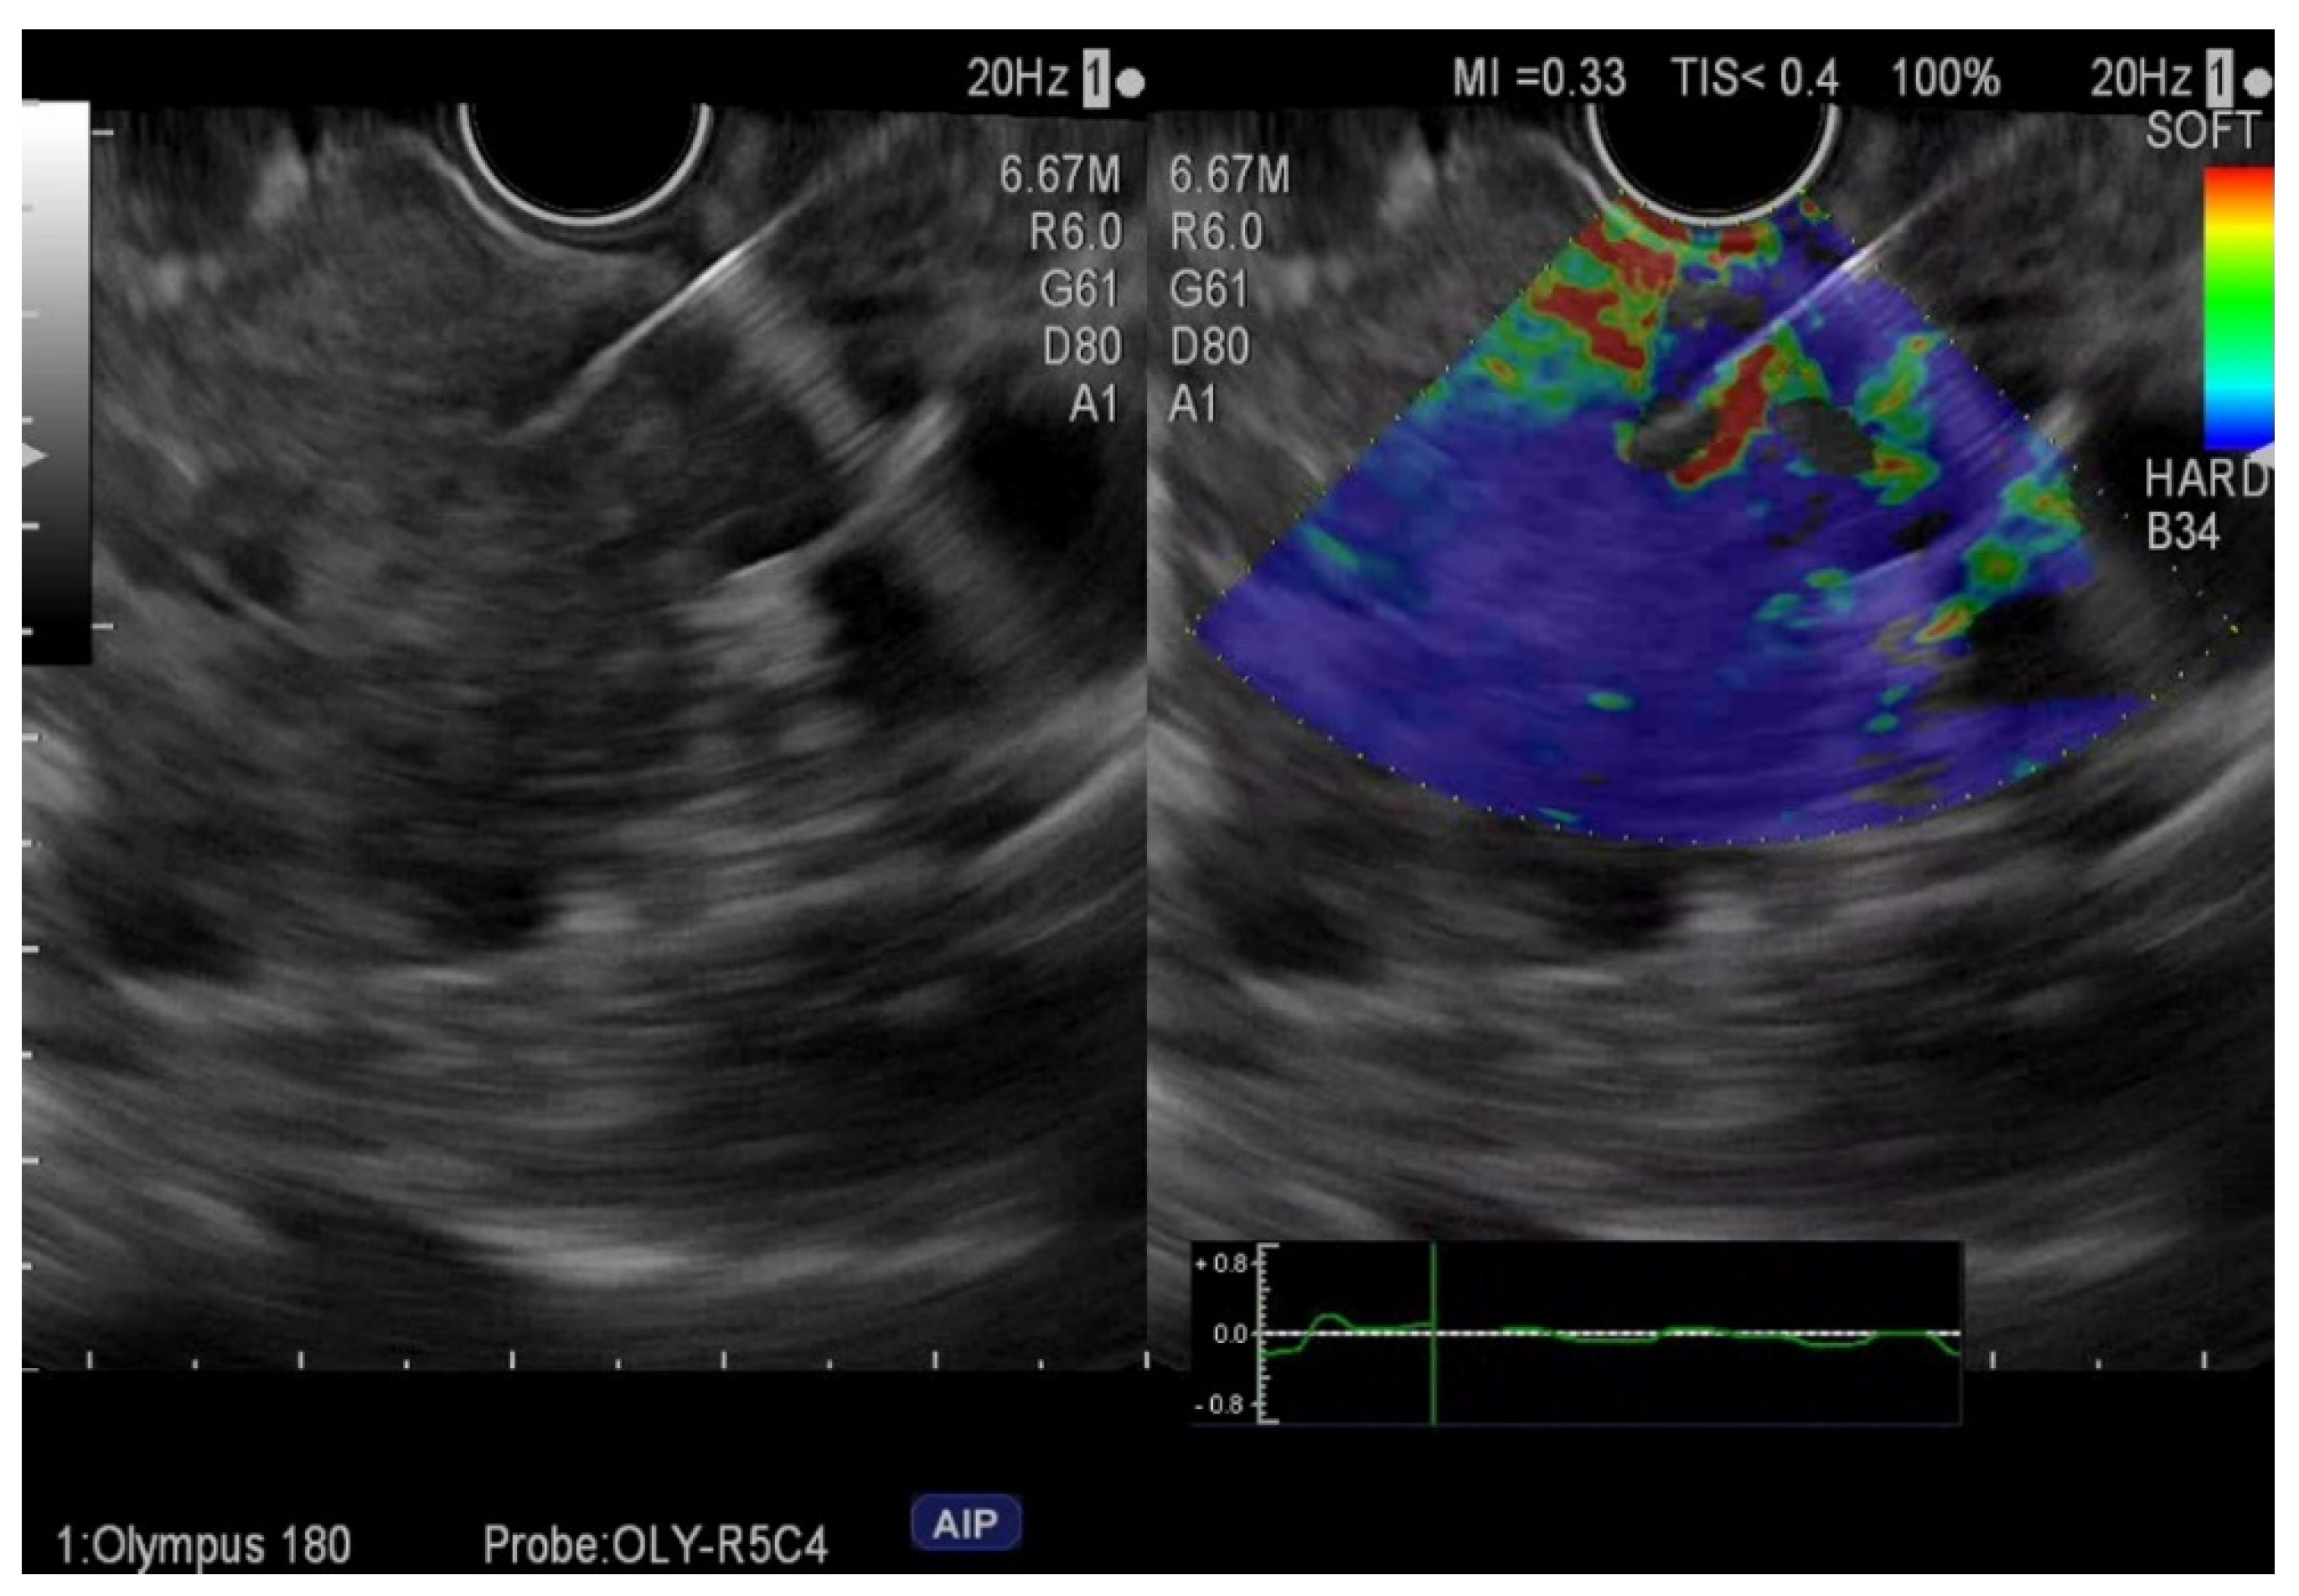

2.4. Procedures